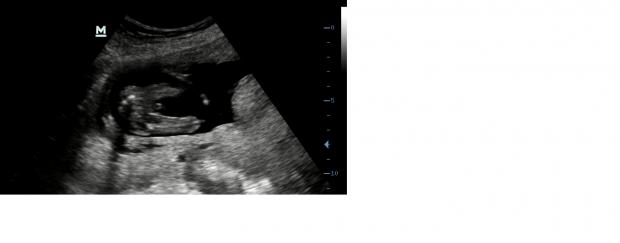

I share three pictures and a video. The video is filmed from the underside of the baby.

I would say a beautifull baby boy!

Looks like a boy

First one is definitely boy

I would go with boy! It looks a lot like my boys' ultrasounds.